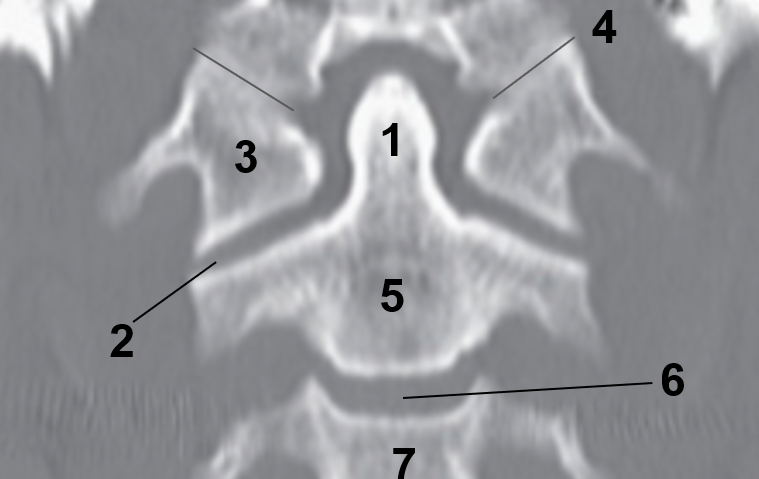

1?

Nasal Bone

2?

Maxillary Sinus

3?

External Acoustic Meatus

4?

Pons

5?

Cerebellum

6?

Mastoid Air Cells

7?

Mandibular Condyles

8?

Sphenoid Bone

9?

Maxillary Bone